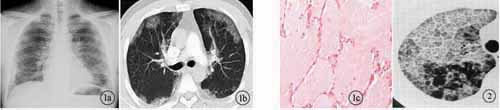

2.1 多层CT表现 本组共6例经病理学证实为PAP患者,其多层CT诊断结果分别为:特发性肺间质纤维化2例;浸润型肺结核1例;肺泡癌1例;肺炎1例;肺泡蛋白沉积症1例,诊断正确率17%。6例患者均见双肺散在分布的毛玻璃样高密度影,密度欠均匀,形态呈三角形、方形和多边形,少数呈圆形、弧形或线形,全部病灶边界清楚。其中4例可见部分病灶融合呈片块状。所有患者病变分布以肺门区及肺野外带为主,上下肺叶均可见到,在周围正常肺组织衬托下,呈地图样(geographic pattern)表现[2,3],见图1a、图1b。4例患者的HRCT图像还可见到在斑片状毛玻璃影中增多、增粗、紊乱的肺小叶间隔,呈铺路石样(crazy paving appearance)表现[4'5],见图2。病变与周围肺组织分界清楚,相邻肺组织未见明显异常表现。本组所有病例未见支气管气像,MSCT增强扫描均未见病灶强化以及纵隔或肺门淋巴结肿大征象。心脏大小形态在正常范围。

2.2 病理学表现 病理学发现此6例患者肺泡腔内充满大量粉红色云絮状、无定形蛋白样物质,见图1c。4例患者病变区内见小叶间隔水肿、增厚,可见淋巴细胞浸润。所有患者肺泡间隔无明显纤维组织增生以及肺泡结构未见破坏。全部病例肺灌洗均可见乳白色牛奶样混浊液,3例可见沉淀物。全部病例过碘酸雪夫(PAS)染色均为阳性,奥辛蓝(AB)染色均为阴性。

图1 患者,男,35岁。a:胸部后前位片,双肺内散在分布的不规则毛玻璃样高密度影,密度欠均匀,边界尚清;b:MSCT增强肺窗图像,双侧肺野外带及肺门区见三角形、方形或多边形毛玻璃样高密度影,密度欠均匀,边界清楚,在周围正常肺组织衬托下,呈地图样表现;c:右下肺穿刺活检标本病理玻片示肺泡内充满大量粉红色无定形蛋白样物质,肺泡结构正常,未见炎性细胞浸润(HE×100) 图2 患者,男,55岁。HRCT示右肺毛玻璃影中见增厚的小叶间隔,呈铺路石样表现